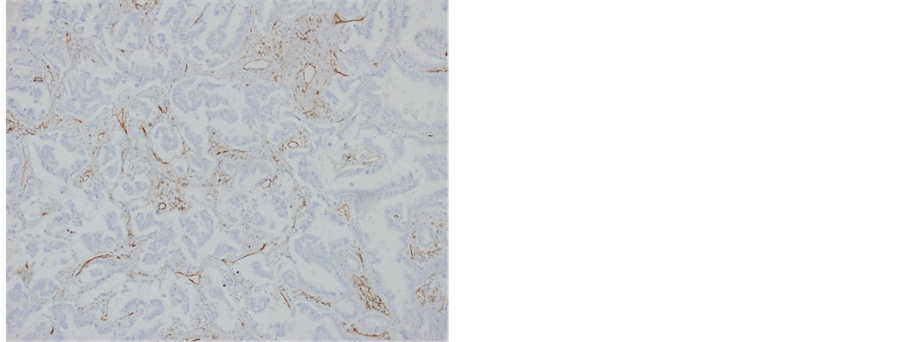

To detect the expression of β-Tubulin-III, immunohistochemistry was employed. Tumor cells of both AAH and AIS patients showed negative expression of β-Tubulin-III. In addition, adherent adenocarcinoma of MIA and IA group showed negative expression of β-Tubulin-III. Alveolar adenocarcinoma in MIA and IA groups that was surrounded by basement membranes had positive expression of β-Tubulin-III (Figure 1(c) and Figure 3(a)). Invasive alveolar adenocarcinoma that was not surrounded by basement membranes showed strong positive expression of β-Tubulin-III (Figure 1(d) and Figure 3(b)). Other invasive cancers such as papillary adenocarci- noma, micropapillary adenocarcinoma and solid adenocarcinoma showed strong positive expression of β-Tub- ulin-III (Figures 3(c)-(f)). Noncancerous alveolar tissues and mucinous adenocarcinoma showed negative expression of β-Tubulin-III. Statistical analysis showed that the average β-Tubulin-III-positive expression score of IA patients was significantly higher than those of AAH, AIS and MIA patients (P < 0.05) (Table 2). These results indicate that invasive cancers such as alveolar adenocarcinoma, papillary adenocarcinoma, micropapillary adenocarcinoma and solid adenocarcinoma have strong positive expression of β-Tubulin-III, while AAH, AIS and the AIS component of MIA, and invasive mucinous adenocarcinoma have negative expression of β-Tubulin- III.

Figure 3. Immunohistochemical staining of β-Tubulin-III in (a) alveolar adenocarcinoma of MIA in the same region shown in Figure 1(c) (×100), (b) adherent adenocarcinoma (upper half) and alveolar invasive adenocarcinoma (lower half) in the same region shown in Figure 1(d) (×50), (c) alveolar adenocarcinoma that invaded pleura and micropapillary adenocarcinoma of the alveolar cavity (×50), (d) papillary adenocarcinoma (×100), (e) micropapillary adenocarcinoma (×100), and (f) solid adenocarcinoma (×200).